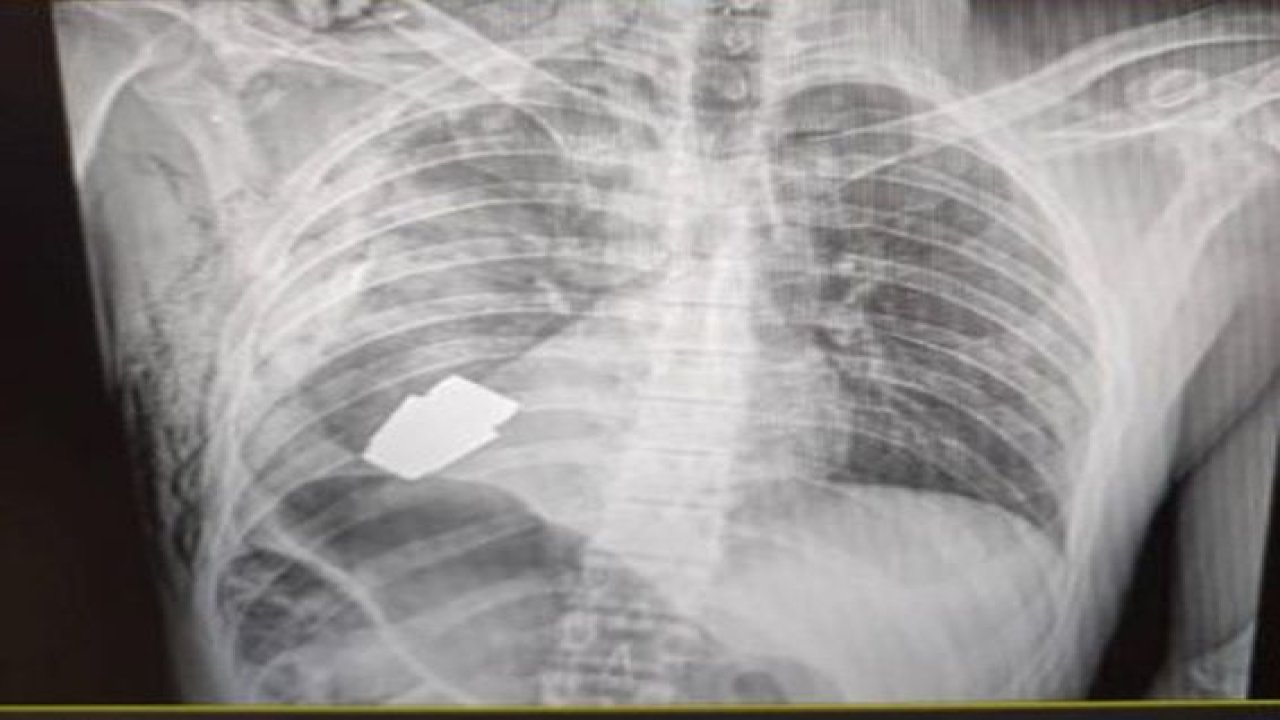

Ukraynalı askerin vücudundan el bombası çıkarıldı